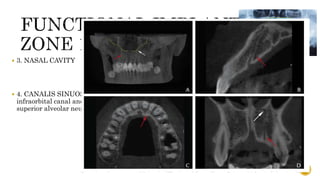

 Also knownas the “traumatic zone”  2. NASOPALATINE / INCISIVE CANAL  Importance- carries nasopalatine nerve and vessels  Normal anatomy  Variations- a) Angulation b) Number  Complication- if an implant contacts neural tissue in this canal, it could lead to failure of osseointegration or sensory dysfunction. 62

 3. NASALCAVITY  4. CANALIS SINUOSUS - is a bone canal in the maxilla that branches from the infraorbital canal and ends laterally to the anterior nasal spine and contains the anterior superior alveolar neurovascular bundles 63